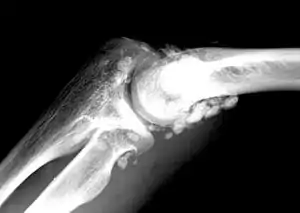

![]() | |

| X-ray of an elbow affected by synovial chondromatosis | |